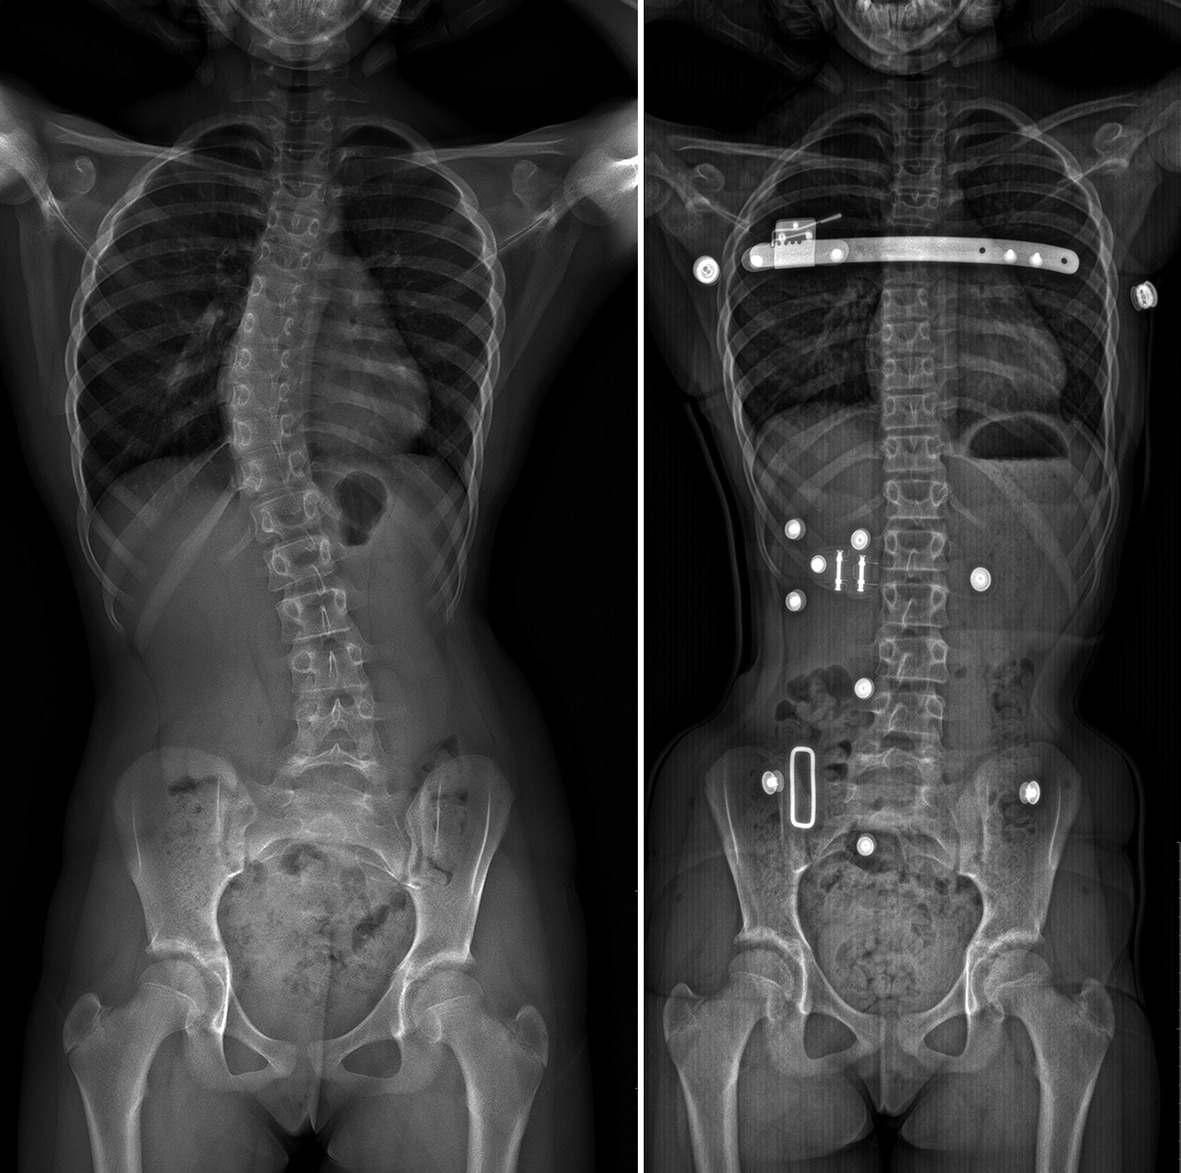

La découverte d’une gibbosité impose une radiographie du rachis en totalité debout de face et de profil (fig. 3). Il ne faut pas se contenter de clichés segmentaires.

Le traitement chirurgical est le plus souvent synonyme de l’échec du dépistage et de la prise en charge orthopédique bien conduite. Les déformations sévères de l’enfant et de l’adolescent peuvent malgré tout bénéficier de techniques toujours plus efficaces qui permettent d’obtenir des corrections importantes avec une bonne maîtrise des risques opératoires.6 Le segment rachidien déformé est alors définitivement corrigé et enraidi au moyen d’un matériel métallique permettant d’obtenir une fusion osseuse et une correction pérenne.